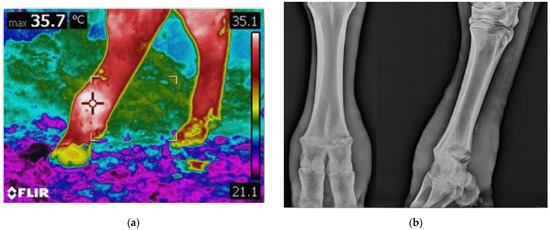

2.2. On Field Thermographic and Radiographic Imaging Acquisition, and Clinical Evaluations